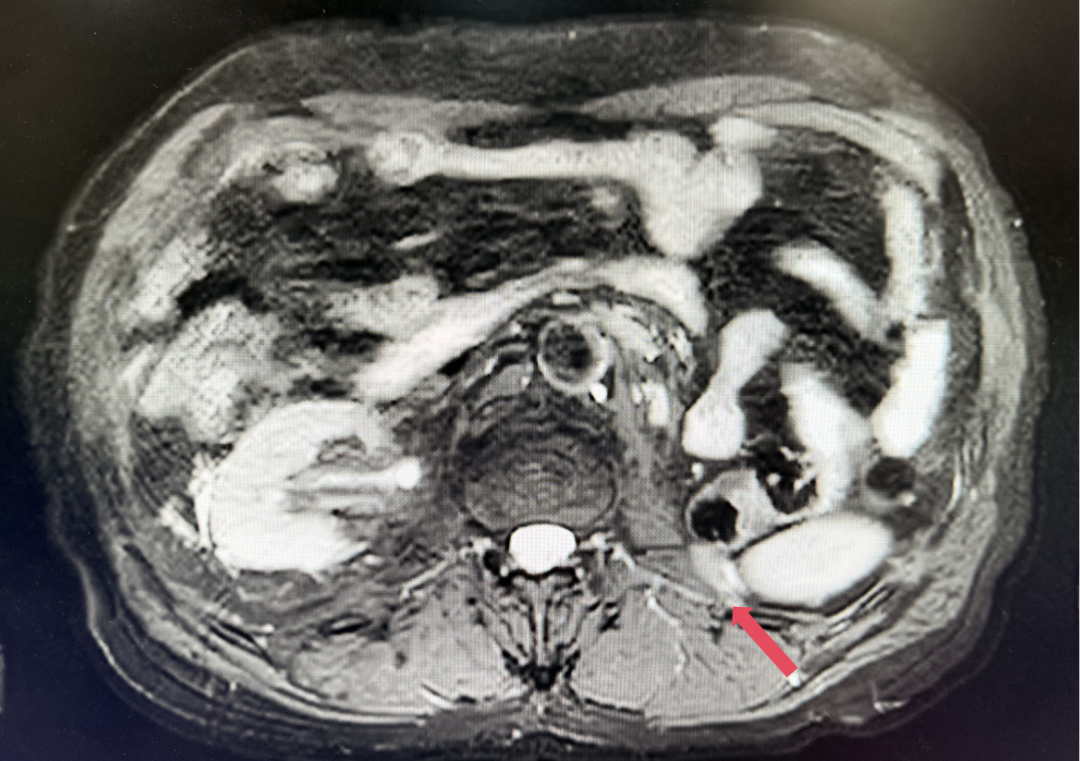

2023年3月:用药6周(C2)后首次肿评,肿瘤负荷减少至76.8mm,达到PR。

2023年3月,初始应答

患者初诊时68岁,2020年9月因“体检发现左肾占位2年”行腹腔镜下左肾根治性切除术,术后病理提示为肾透明细胞癌,pT3aN0M0,未行术后辅助治疗、未规律复查。2022年3月胸腹盆CT示腹膜后转移,IMDC评分0分,低危组。随后予一线培唑帕尼治疗,最佳疗效SD,2022年11月PD。于2023年1月经筛选进入Ⅲ期FRUSICA-2临床研究,开始接受呋喹替尼联合信迪利单抗二线治疗,用药6周(C2)后首次肿评即实现疗效PR(缩瘤率40.2%),用药10个月时缩瘤率近七成(68%),并维持上述水平至今,PFS已经超过37个月,在二线治疗中实现了长期无进展生存。同时,患者对呋喹替尼联合信迪利单抗方案耐受性良好,仅见轻微蛋白尿和偶然腹泻,未见其他不良反应,也未见免疫治疗相关不良反应。该方案有望为TKI经治的晚期肾癌患者带来新的选择,为实现长期生存提供可能性。